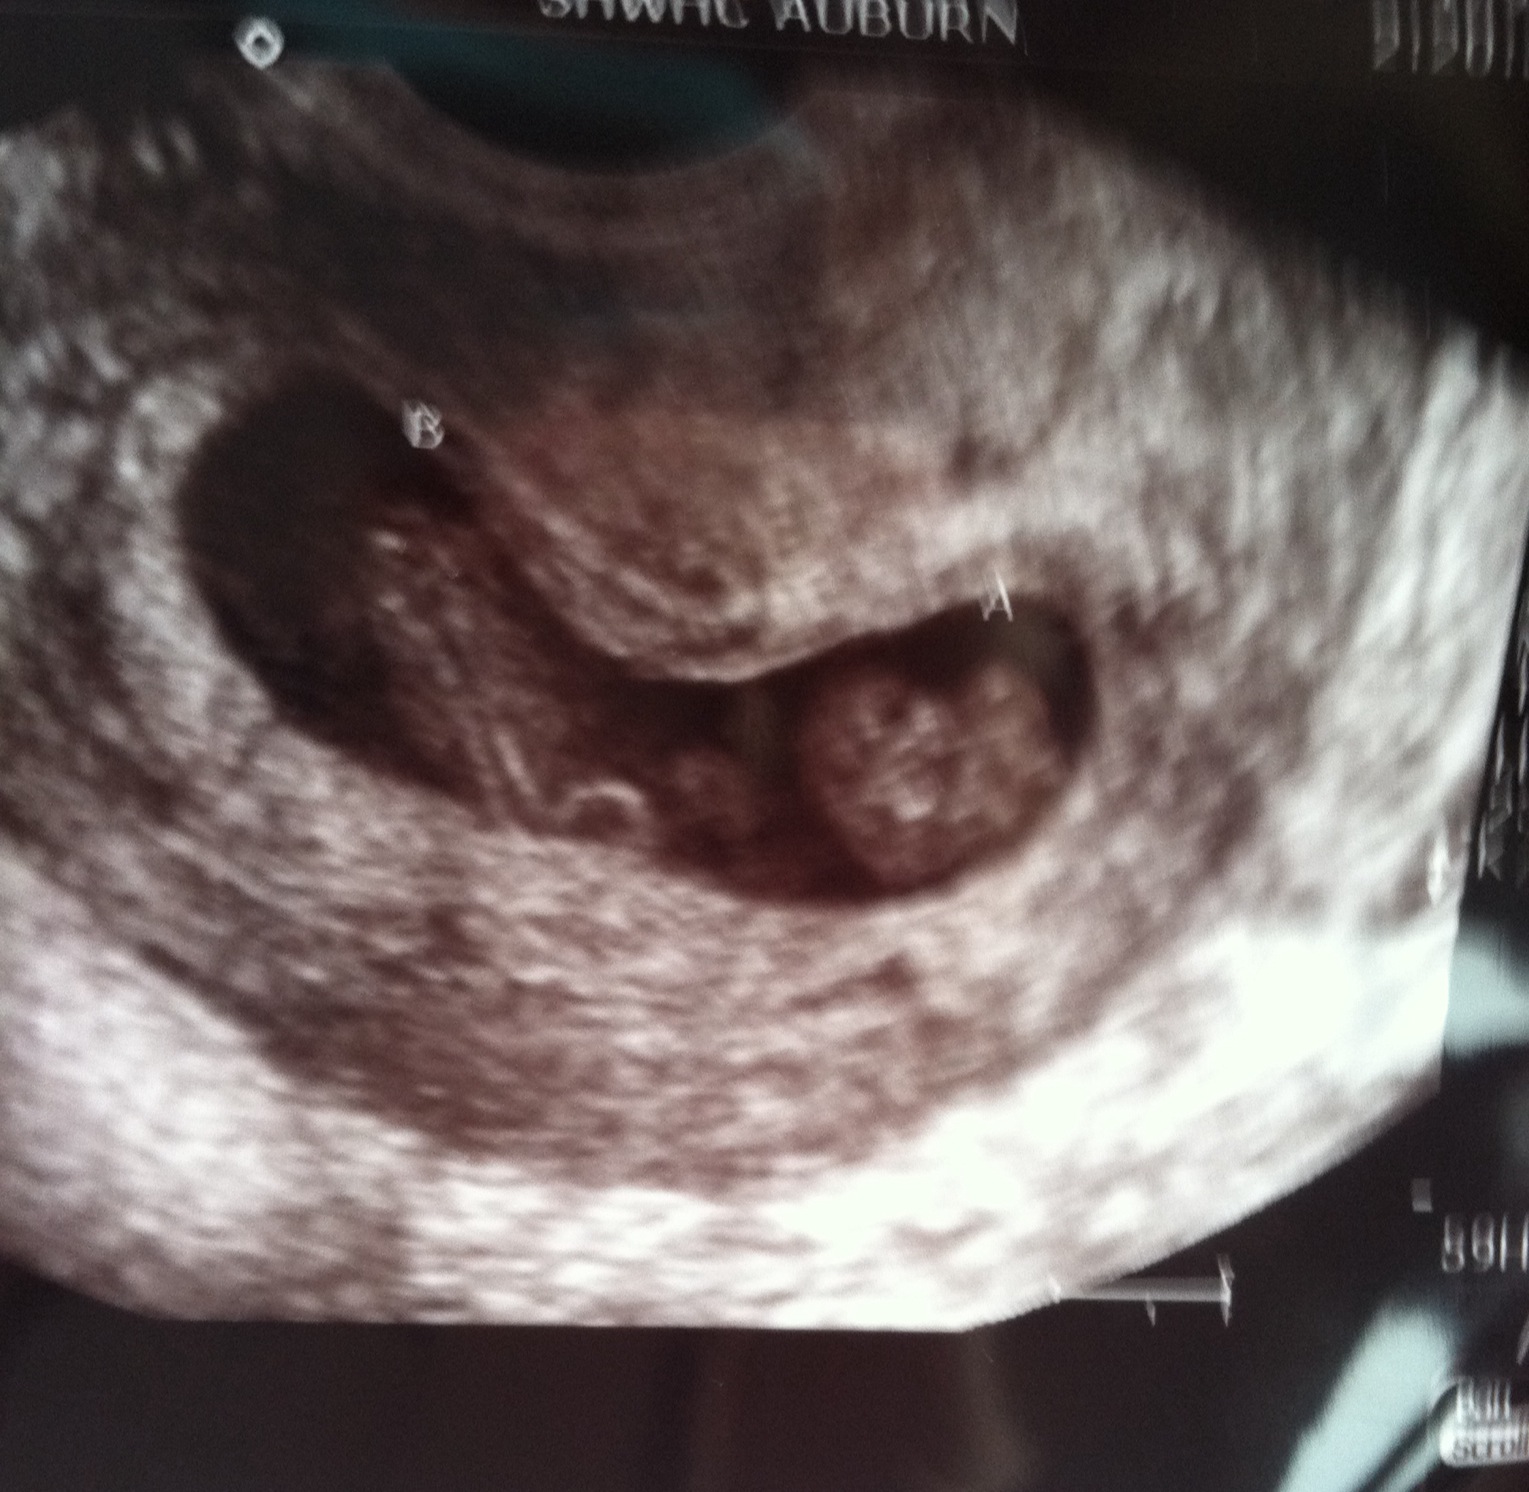

Still in shock here. Had our first appointment yesterday, which they told us was just for a pelvic exam and blood work. Well my uterus was tilted so the doctor opted to do an ultrasound. The ultrasound tech told us to hold our breath...there's two! They think they're identical, and we weren't doing any fertility treatments. So this was QUITE unexpected, but we're very excited!